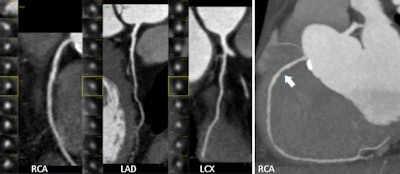

The protocol required adding up the number of involved coronary segments (segment involvement score) for each patient, and measuring the CCS at CCTA. CCTA-detected plaque was characterized as calcified or noncalcified, and graded stenosis in each segment in plaque was present at 50% or less luminal narrowing as mild, 50% to 70% as intermediate, and 70% or greater as high-grade stenosis.

As for disease severity in these asymptomatic individuals, CT showed that 15.6% had plaques without stenosis, 23.9% had mild plaque, 10.7% had intermediate plaque, and 21.5% had high-grade stenosis of 70% narrowing or greater, the authors reported. A zero calcium score didn't mean the arteries were clear.

In fact, plaque was found in 43% of patients, and noncalcified plaques were seen in 100 (32.7%) of all patients with zero calcium scores.